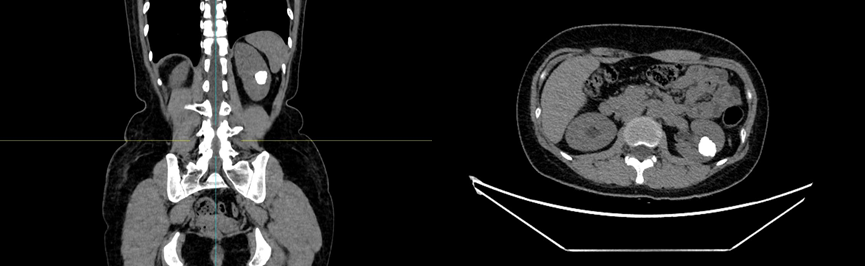

肾盏憩室结石是一种泌尿系统疾病,通常发生在肾脏的憩室内。憩室指的是肾脏皮质或肾盏的局部膨出,形成的小型囊状结构。其内因尿液滞留,容易形成结石。这类结石可能引发肾绞痛、尿路感染甚至肾功能损害。临床表现常为腰痛、尿频、尿急等症状,若结石较大,可能导致尿路梗阻。影像学检查如CT或超声可帮助诊断。在治疗方法上主要包括药物治疗、体外冲击波碎石及手术治疗等。在日常生活中,保持充足的水分摄入,预防尿液浓缩,有助于降低结石形成风险。同时,定期体检和早期干预对于延缓疾病进展起到了至关重要的作用。